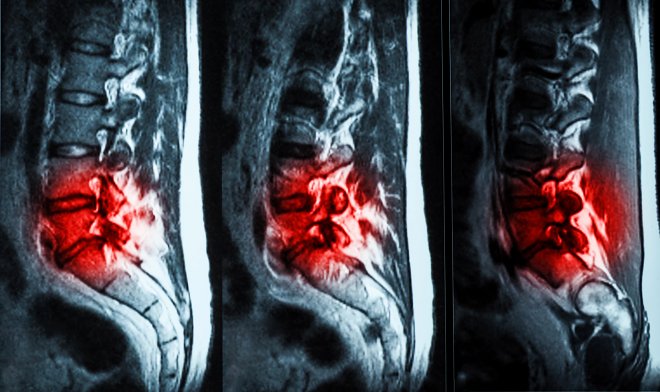

Перед применением гель нагревают, превращая в густую жидкость, которая затем вводится шприцем в пораженные диски. Там, охладившись до температуры тела, она формирует имплант, по своим характеристикам почти ничем не уступающий межпозвоночному диску. Для оценки результата восстановления требуется еще полгода наблюдения у врача.

Уже есть первые обнадеживающие результаты. Используя 10-бальную шкалу, испытуемые отметили снижение болевых ощущений с 7,1 до 2,0, а боль, препятствующая заниматься повседневной деятельностью, «упала» с 48 до 6.